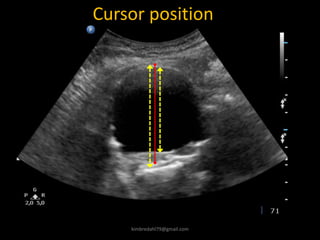

Cursor position

kimbredahl79@gmail.com

Diameter assessment – when to measure

Cardiac cycle

Upper LoA =4.7 mm

Challenges in systoly

Diameter

forskel

Tid

1 sekund

Frame rate = 18

By Henrik Sillesen